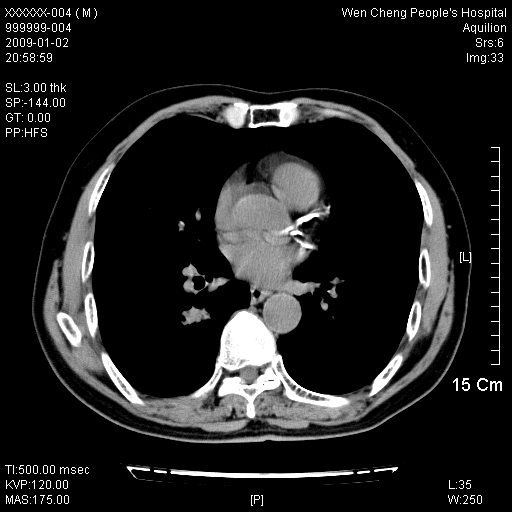

男性,73岁,有慢支病史,肿瘤系列标志物检验正常,血沉及血常规正常

右肺下叶背段小片状 磨玻璃样模糊影,内见血管及含气支气管像,支气管管壁增厚。考虑:慢性炎症!

1)不排除右肺下叶周围型肺癌可能;建议追踪复查。2)左右冠状动脉钙化。

右肺下叶背段小片状 实性与磨玻璃样影,内见血管及含气支气管像,支气管管壁增厚,边缘见长毛刺影。考虑:慢性炎症或肿瘤!建议抗炎治疗复查,密切观察随访!

右肺下叶片团状影内见扩张的含气支气管和支气管管壁增厚,其周有磨玻璃样模糊影和长毛刺。考虑慢性炎症可能性大。

2、右肺下叶片团状影内见扩张的含气支气管和支气管管壁增厚,其周有磨玻璃样模糊影和长毛刺。考虑周围型肺ca可能,结核不排。

高度提示细支气管肺泡癌,建议抗炎治疗半月观察病灶变化,如无明显改变,建议立即手术治疗.